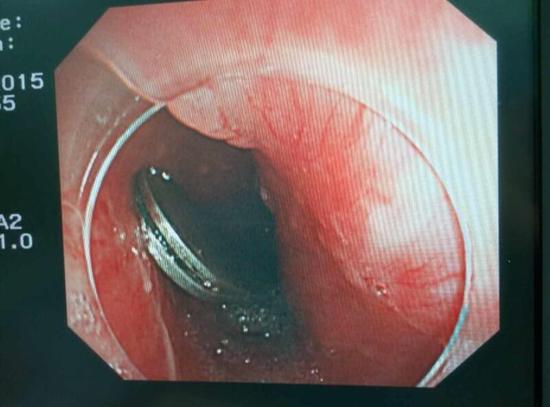

手術(shù)中,范醫(yī)生通過胃鏡準(zhǔn)確發(fā)現(xiàn)了胃里的鑷子。但讓他驚訝的是,在華先生胃底竟然還躺著三個(gè)被腐蝕了的打火機(jī),打火機(jī)的金屬部件都已經(jīng)不見了。

隨后,范醫(yī)生先用圈套器套取出了長10厘米的鑷子,再一個(gè)一個(gè)地取出了打火機(jī)。整個(gè)取出過程小心謹(jǐn)慎而又一氣呵成,只用了不到10分鐘。

“真的是太危險(xiǎn)了?!狈夺t(yī)生表示,鑷子前端比較尖銳,一旦刺穿胃前壁,又有可能刺破肝臟,引發(fā)臟器受損和大出血。而打火機(jī)在胃內(nèi)酸性胃液腐蝕后,不 僅塑料外殼有毒,打火機(jī)內(nèi)的燃料一旦發(fā)生泄露會(huì)有灼傷胃腸道的危險(xiǎn)。打火機(jī)頭端還有尖銳金屬部件,若嵌頓或劃傷腸道會(huì)誘發(fā)腸梗阻、腸穿孔、消化道出血等嚴(yán) 重并發(fā)癥。